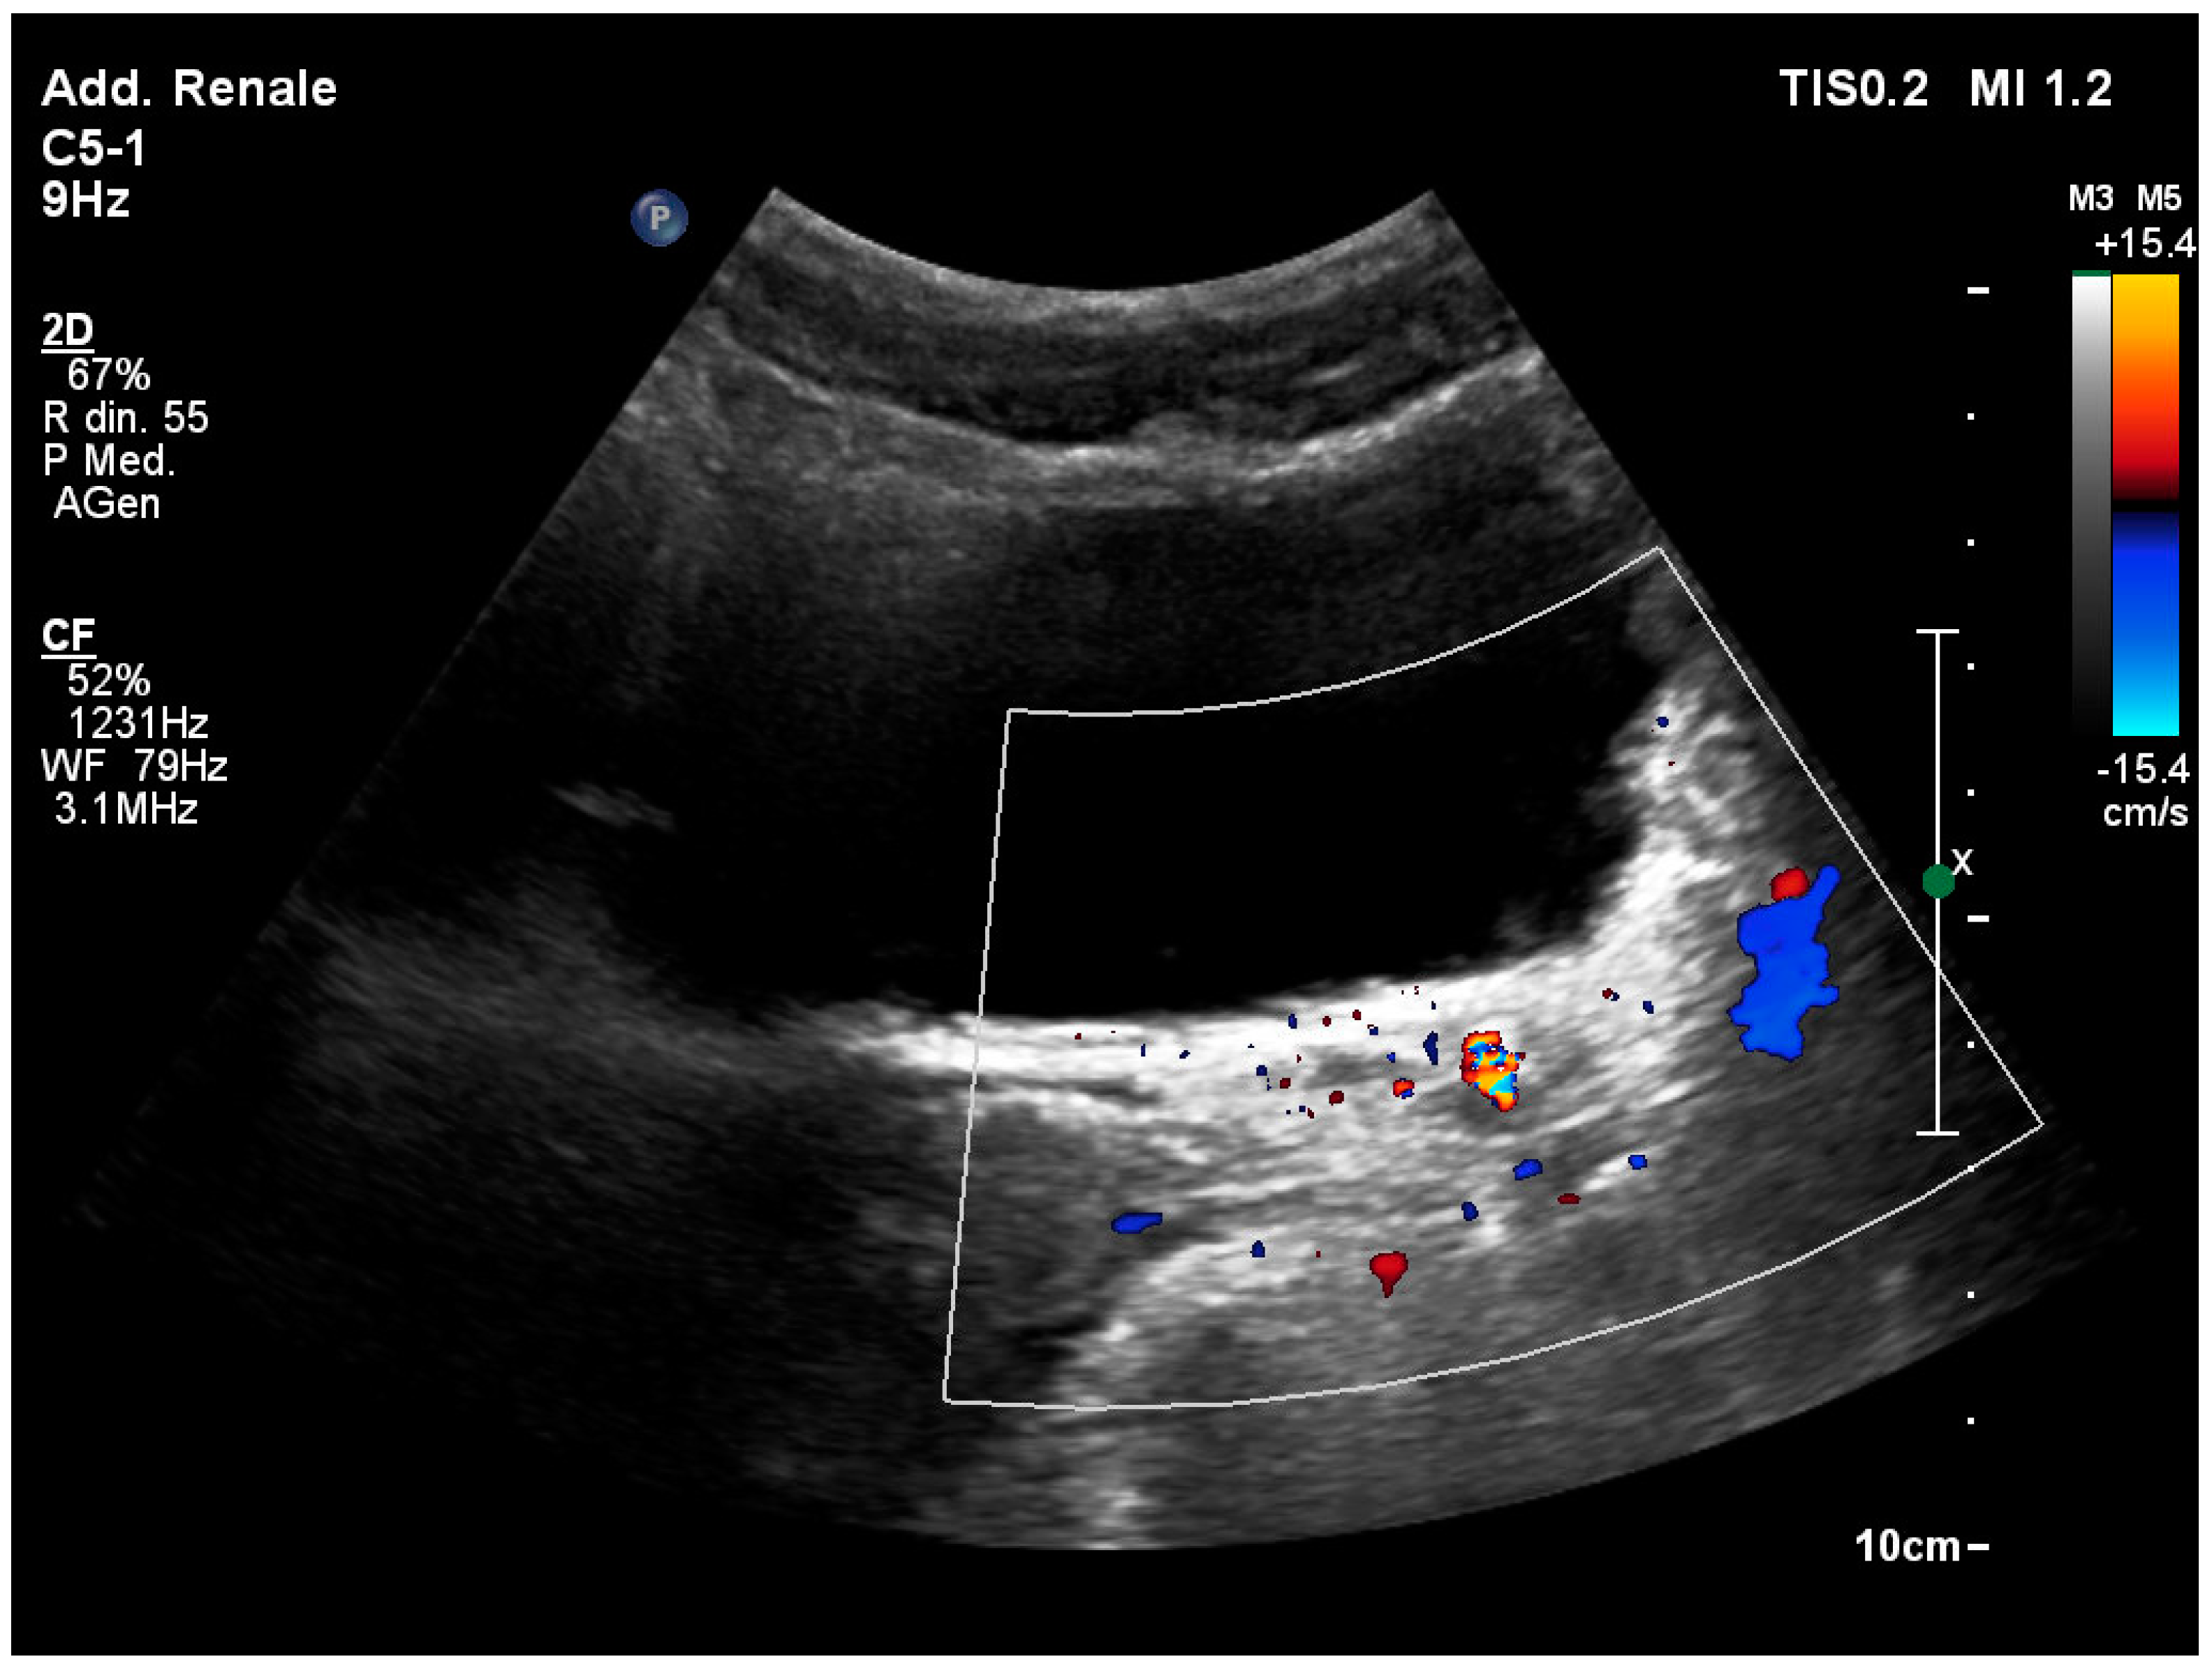

3.7. Identification of the Ureteral Jet

3.8. Ureteropelvic Junction Obstruction